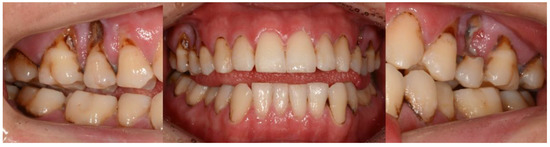

2. Case Report